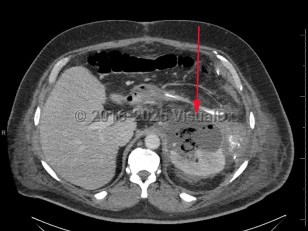

Imaging Studies image of Perinephric abscess - imageId=8360654. Click to open in gallery.  caption: '<span>Axial image from enhanced CT scan of the abdomen and pelvis with a complex left perirenal fluid collection with air, consistent with a perinephric abscess.</span>'

Axial image from enhanced CT scan of the abdomen and pelvis with a complex left perirenal fluid collection with air, consistent with a perinephric abscess.